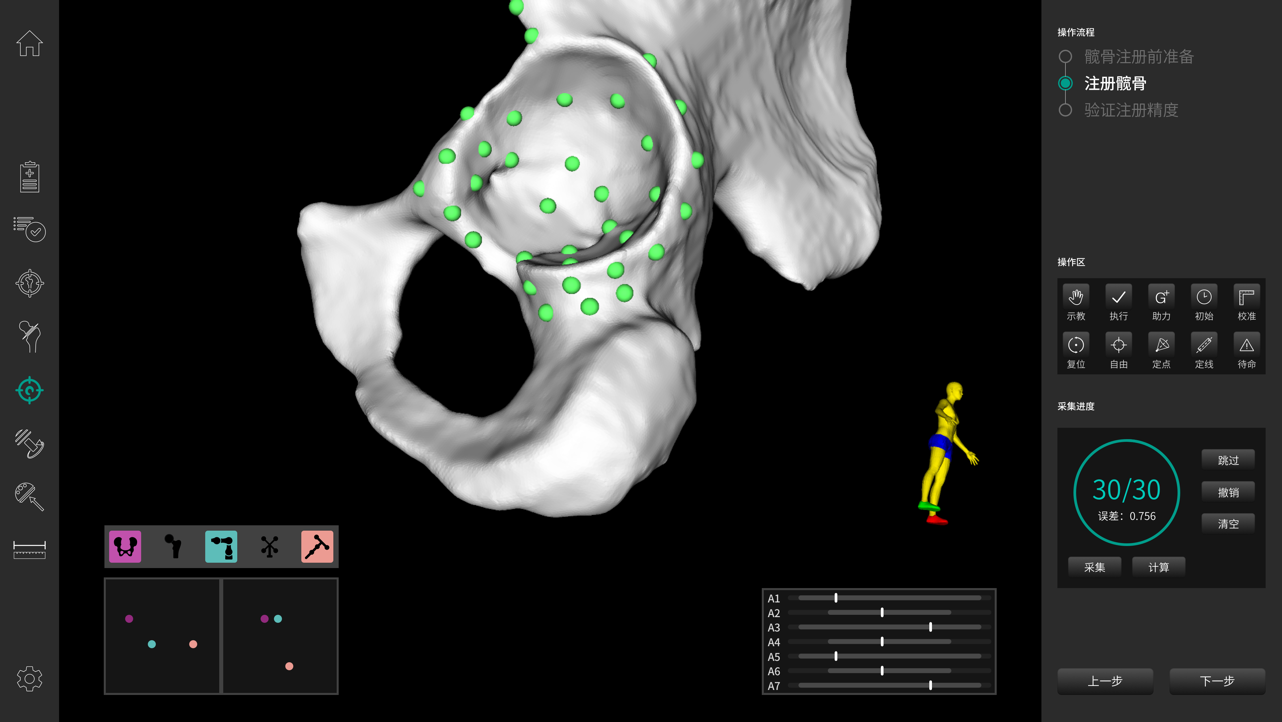

· 注冊(cè)精準(zhǔn)穩(wěn)定。

· 穩(wěn)定快速解剖點(diǎn)配準(zhǔn),將術(shù)中生理結(jié)構(gòu)與其術(shù)前影像數(shù)據(jù)建立空間關(guān)聯(lián),保證手術(shù)規(guī)劃的準(zhǔn)確執(zhí)行。配準(zhǔn)時(shí)間控制在3-5min。